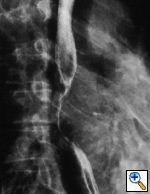

Fig. 26b: Barium swallow showing the displacement of the esophagus by the subcarinal nodes, N2. The presence of the nodes can only be inferred.